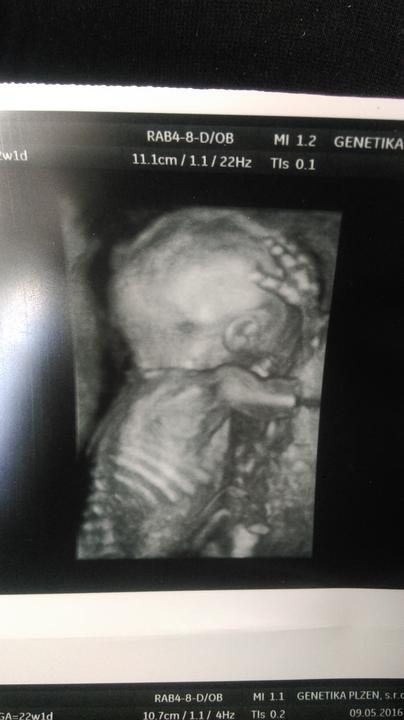

Zítra konečně na screening 🙂 těším se až přítel uvidí toho našeho drobečka 🙂 a že bude vše v pořádku 🙂 byl jste někdo v plzni v Černicich? 🙂 jak jste byli spokojeni? 🙂